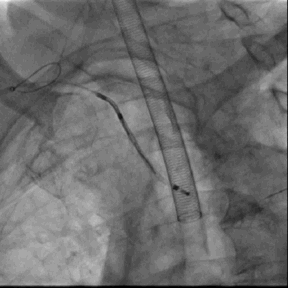

2. 经右桡动脉置入Sentinel CPS系统,释放于头臂干、左颈总动脉位

6. Sentinel CPS系统

Sentinel CPS系统在另一患者中應用捕抓到的左心耳血栓